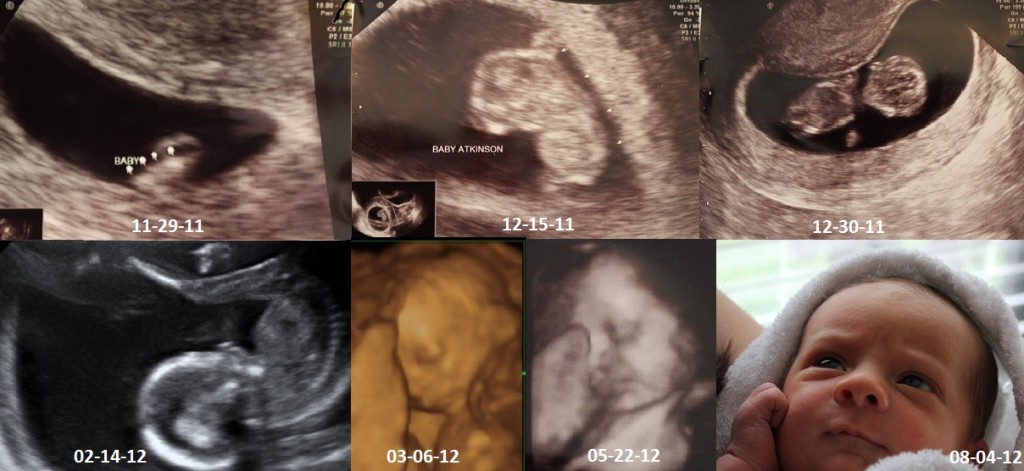

Your ultrasound progression!